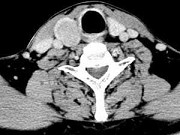

- 单项选择题男,43岁, 右颈部扪及一包块,CT如图所示, 最可能的诊断是 ( )

A、甲状腺腺瘤

B、甲状腺腺癌

C、结节性甲状腺肿

D、甲状腺原发淋巴瘤

E、甲状腺转移瘤